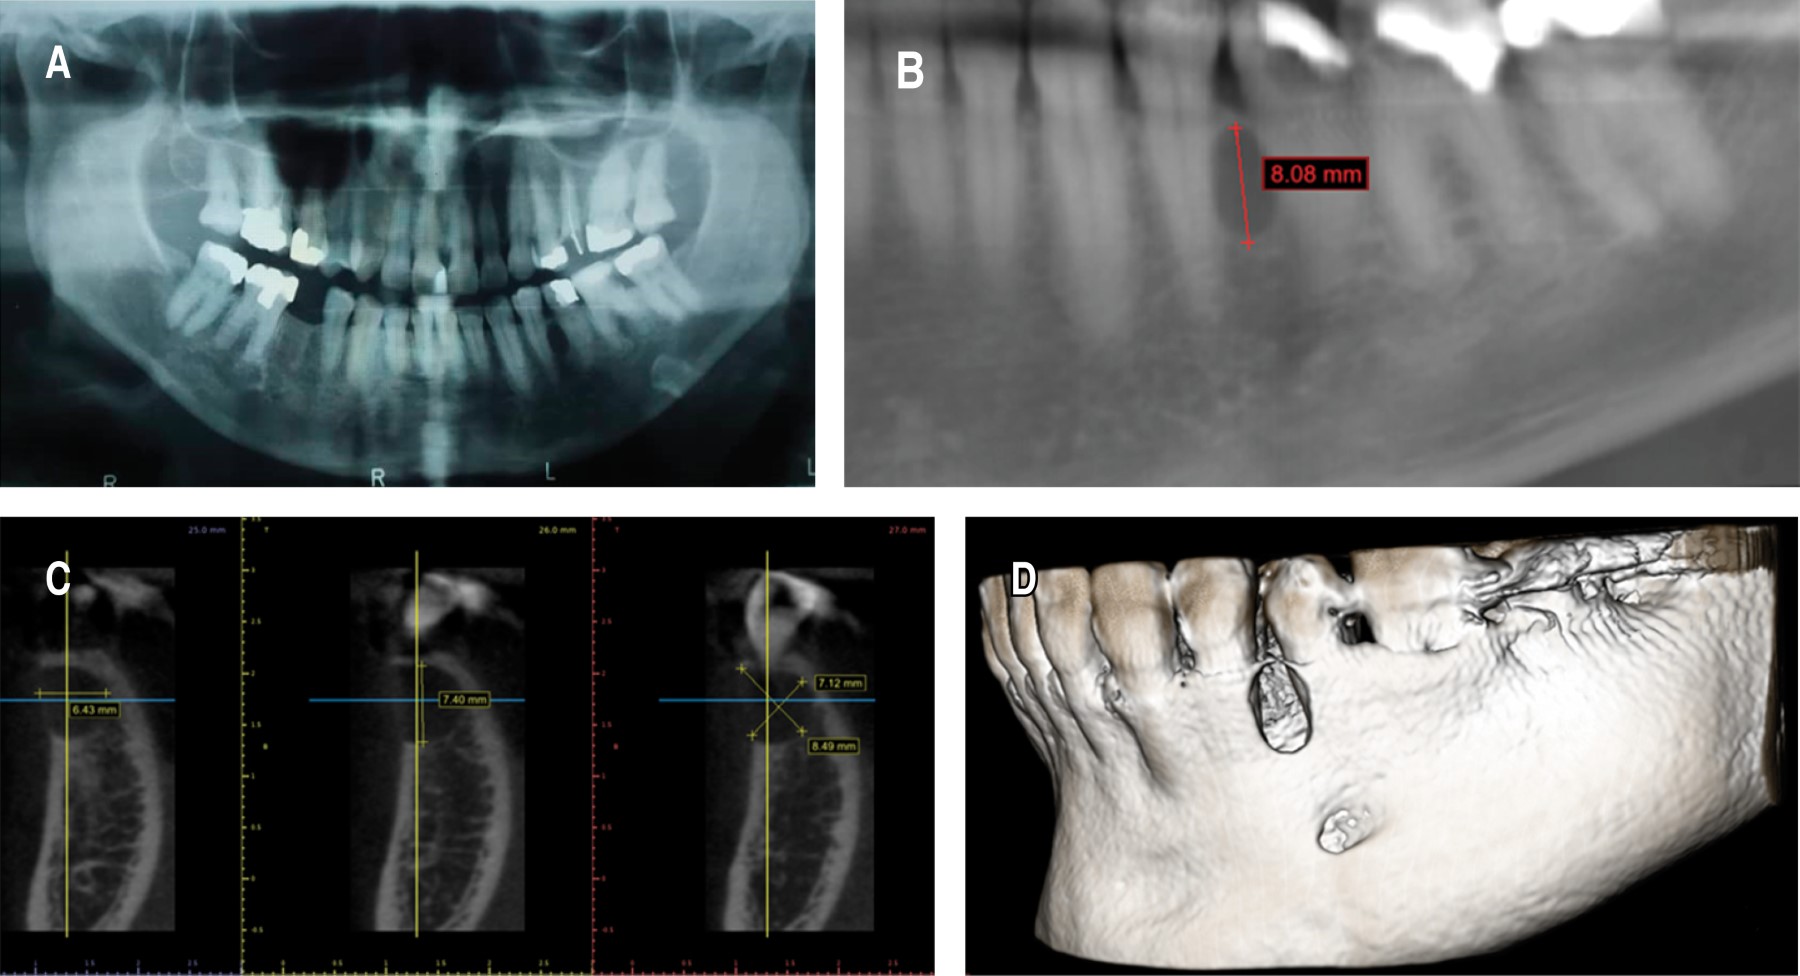

Se realizó biopsia escisional bajo anestesia local con lidocaína a 2%, punción de la zona, donde se obtiene un líquido de coloración ámbar con perlas de las mismas características crómicas, abordaje con incisión crevicular, levantamiento de colgajo mucoperióstico, exposición de la lesión, enucleación, curetaje, osteotomía periférica con márgenes de seguridad de 0.5 mm, abundante lavado con solución salina 0.9% y síntesis de tejidos. Se envió la muestra a patólogo bucal y maxilofacial para su estudio (Figura 3).

Figura 3